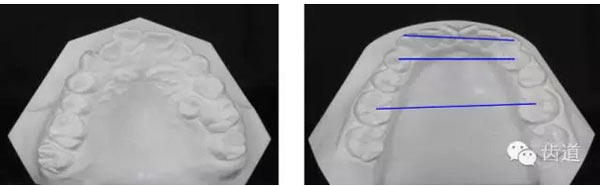

上牙弓:尖圓形,25腭側(cè)完全錯(cuò)位,26前移

下牙弓:卵圓形,下前牙區(qū)擁擠

上牙弓擁擠度9mm;下牙弓擁擠度7mm;

上牙列中線左偏1.5mm,下牙列中線右偏1mm。

Spee曲線1.5mm;前牙開(kāi)合3mm;深覆蓋4mm

Bolton指數(shù):前牙比(78.8±1.72%):80.7%

全牙比(91.5±1.51%):92.9%

Pont指數(shù):

第一前磨牙指數(shù)(82.16±4.22):82.72

第一磨牙指數(shù)(63.36±3.64):64.97

前段寬度 | 中段寬度 | 后段寬度 | |

上牙列 | 31.6mm | 33.2mm | 41.8mm |

下牙列 | 27.6mm | 28.9mm | 39.6mm |

………提示上牙弓較下牙弓狹窄